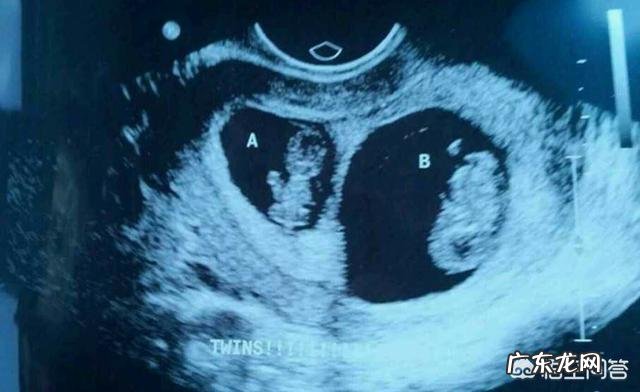

怀双胞胎的人要注意什么?一般怀双胞胎的人会比怀单胎的人更加辛苦,当然也更容易出现意外,因此,怀双胞胎应该格外注意 。

由于怀双胎会比怀单胎风险更大,因此怀双胞胎的人产检会更频繁一些 。当做三维、四维彩超时,双胎孕妈咪产检的时间可能也会更长一些,因为要排除两个宝宝的畸形,自然要花费更多的时间 。当然,医生还会根据孕妈咪的情况,适当增加产检的次数,以便于及时掌握两个胎儿的发育情况 。